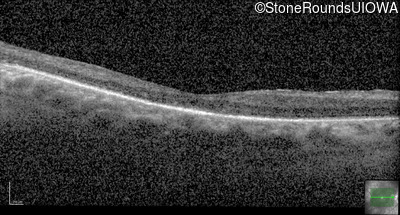

Optical Coherence Tomography - Right - 20/125

Exemplar / OCT Stack

OCT Stack